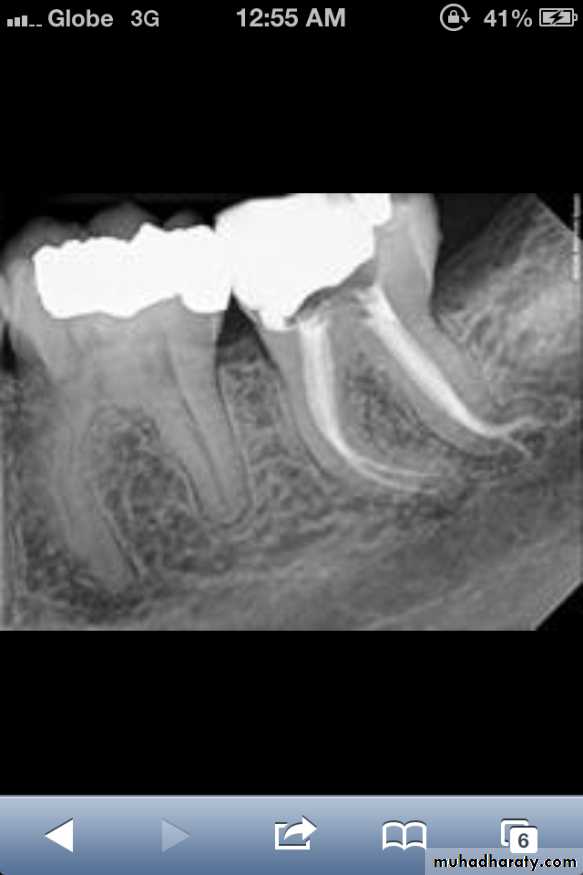

Dental floss abrasion. Note the obliteration of the pulp chambers and reduction in size of the root canals.